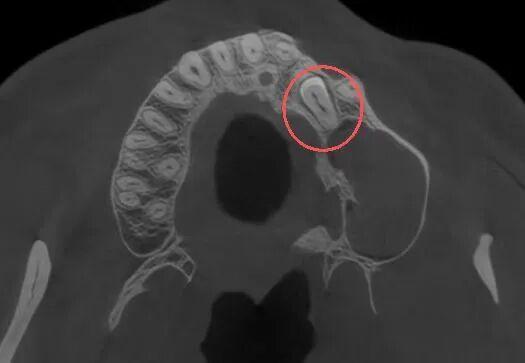

口腔颌面外科医生为其进行了详细的口腔检查并拍了放射片,结果显示:张先生的牙齿属于腭向埋伏阻生双尖牙,更值得注意的是,他的左侧上颌窦底还长有一个丘状软组织囊肿,且阻生牙的牙根与囊肿底部关系十分密切。

“阻生牙是牙齿萌出过程中因空间不足、遗传、感染等多种因素导致的异位埋伏,而上颌窦囊肿则是上颌窦内常见的良性病变,两者同时出现且位置紧密关联,若不及时处理,可能会引发囊肿增大、骨质破坏、上颌窦炎等问题。”口腔颌面外科病房主任孙超解释道。

最终,专家团队决定采用“经拔牙创入路”的创新方案,一次手术解决两个问题。手术中,医生先精准拔掉埋伏牙,利用拔牙后形成的天然通道,将内镜伸进去直达囊肿位置,在清晰视野下把囊肿彻底清除,最后做好伤口缝合和保护。整个过程创伤小,还最大限度保护了上颌窦里的正常组织。